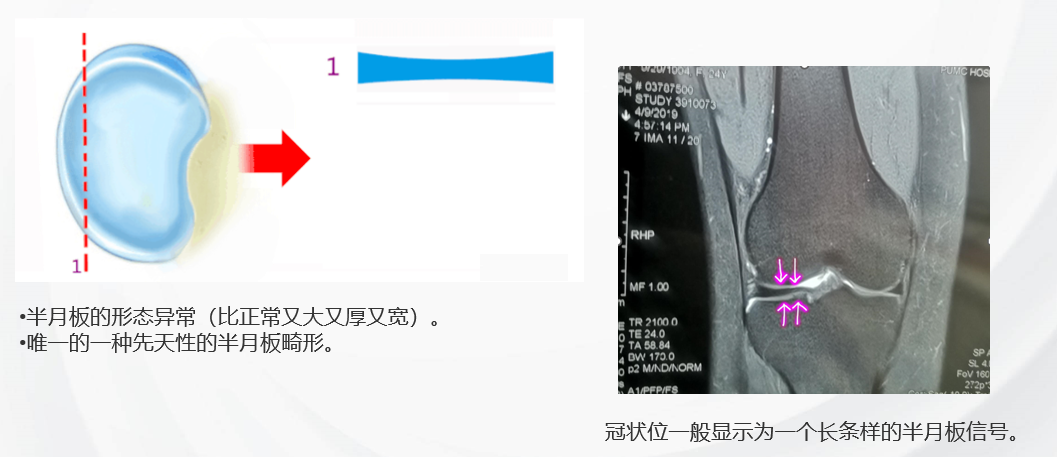

半月板发育畸形

特殊的半月板疾病——先天性盘状半月板